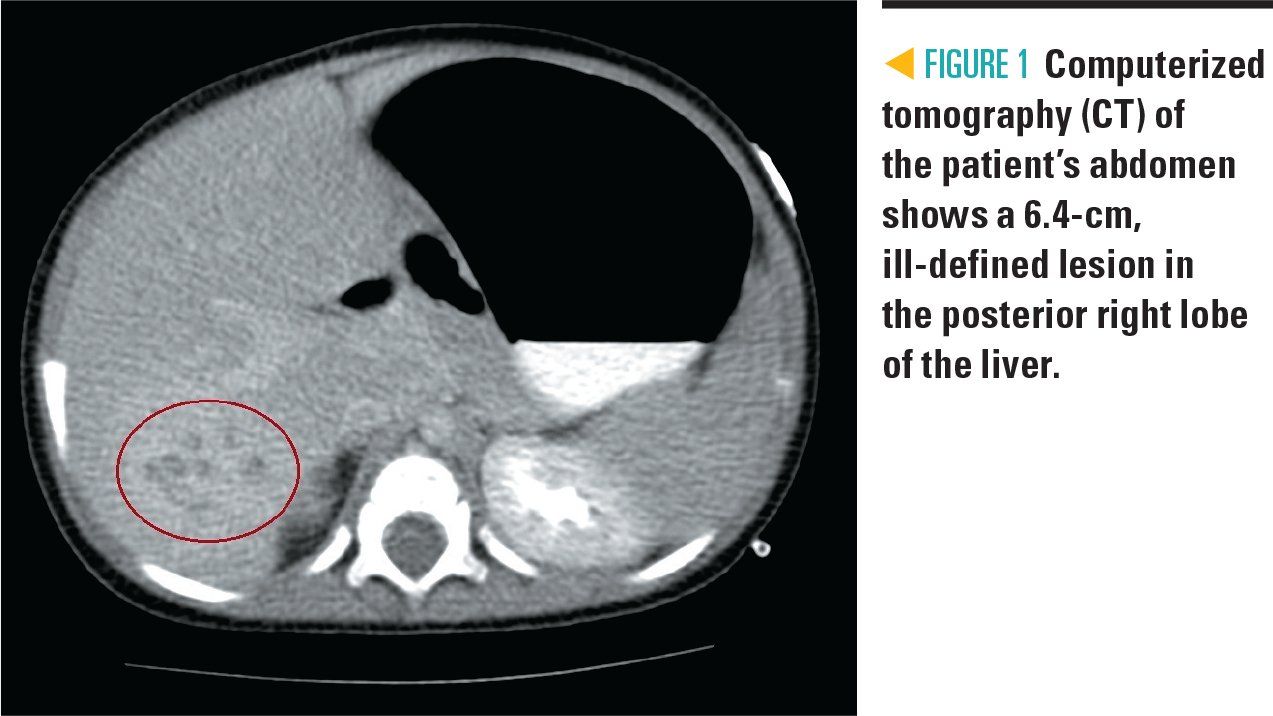

The patient was admitted to the general pediatric unit for febrile neutropenia and was started on cefepime for empiric bacterial antibiotic coverage. Due to potential malignancy, the patient had an abdominal ultrasound that showed a 6.4-cm hepatic mass, confirmed with an abdominal computed tomography (CT) scan (Figure 1).